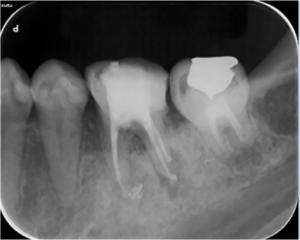

4ヶ月後

根の治療4か月後のレントゲン写真です。骨の溶けている部分の透過性(黒さ)が改善して(薄くなって)、治癒に向かっている様子がうかがえます。治療後から咬む際の痛みなどの症状は無くなり、治療後2カ月で仮歯を装着されています。

9ヶ月後

根の治療9か月後のレントゲン写真です。矢印の根の先の骨の溶けている部分は無くなっています。この後、仮歯からジルコニア製のかぶせを装着されました。

治療後

奥歯は複数の根があり、根の病気になるとなかなか治癒させるのが難しいです。しかし、原因となる根の中のばい菌をしっかり除去し、抗菌性のある材料で根の中をつめるとこのように治癒に導くことができます。治療の初期に症状が全くなくなったため、患者様はとても喜ばれておられました。